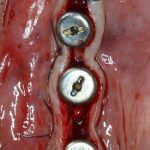

Откроем область операции и посмотрим, что там:

Вроде как, всё неплохо. Наверное, можно поставить имплантаты?